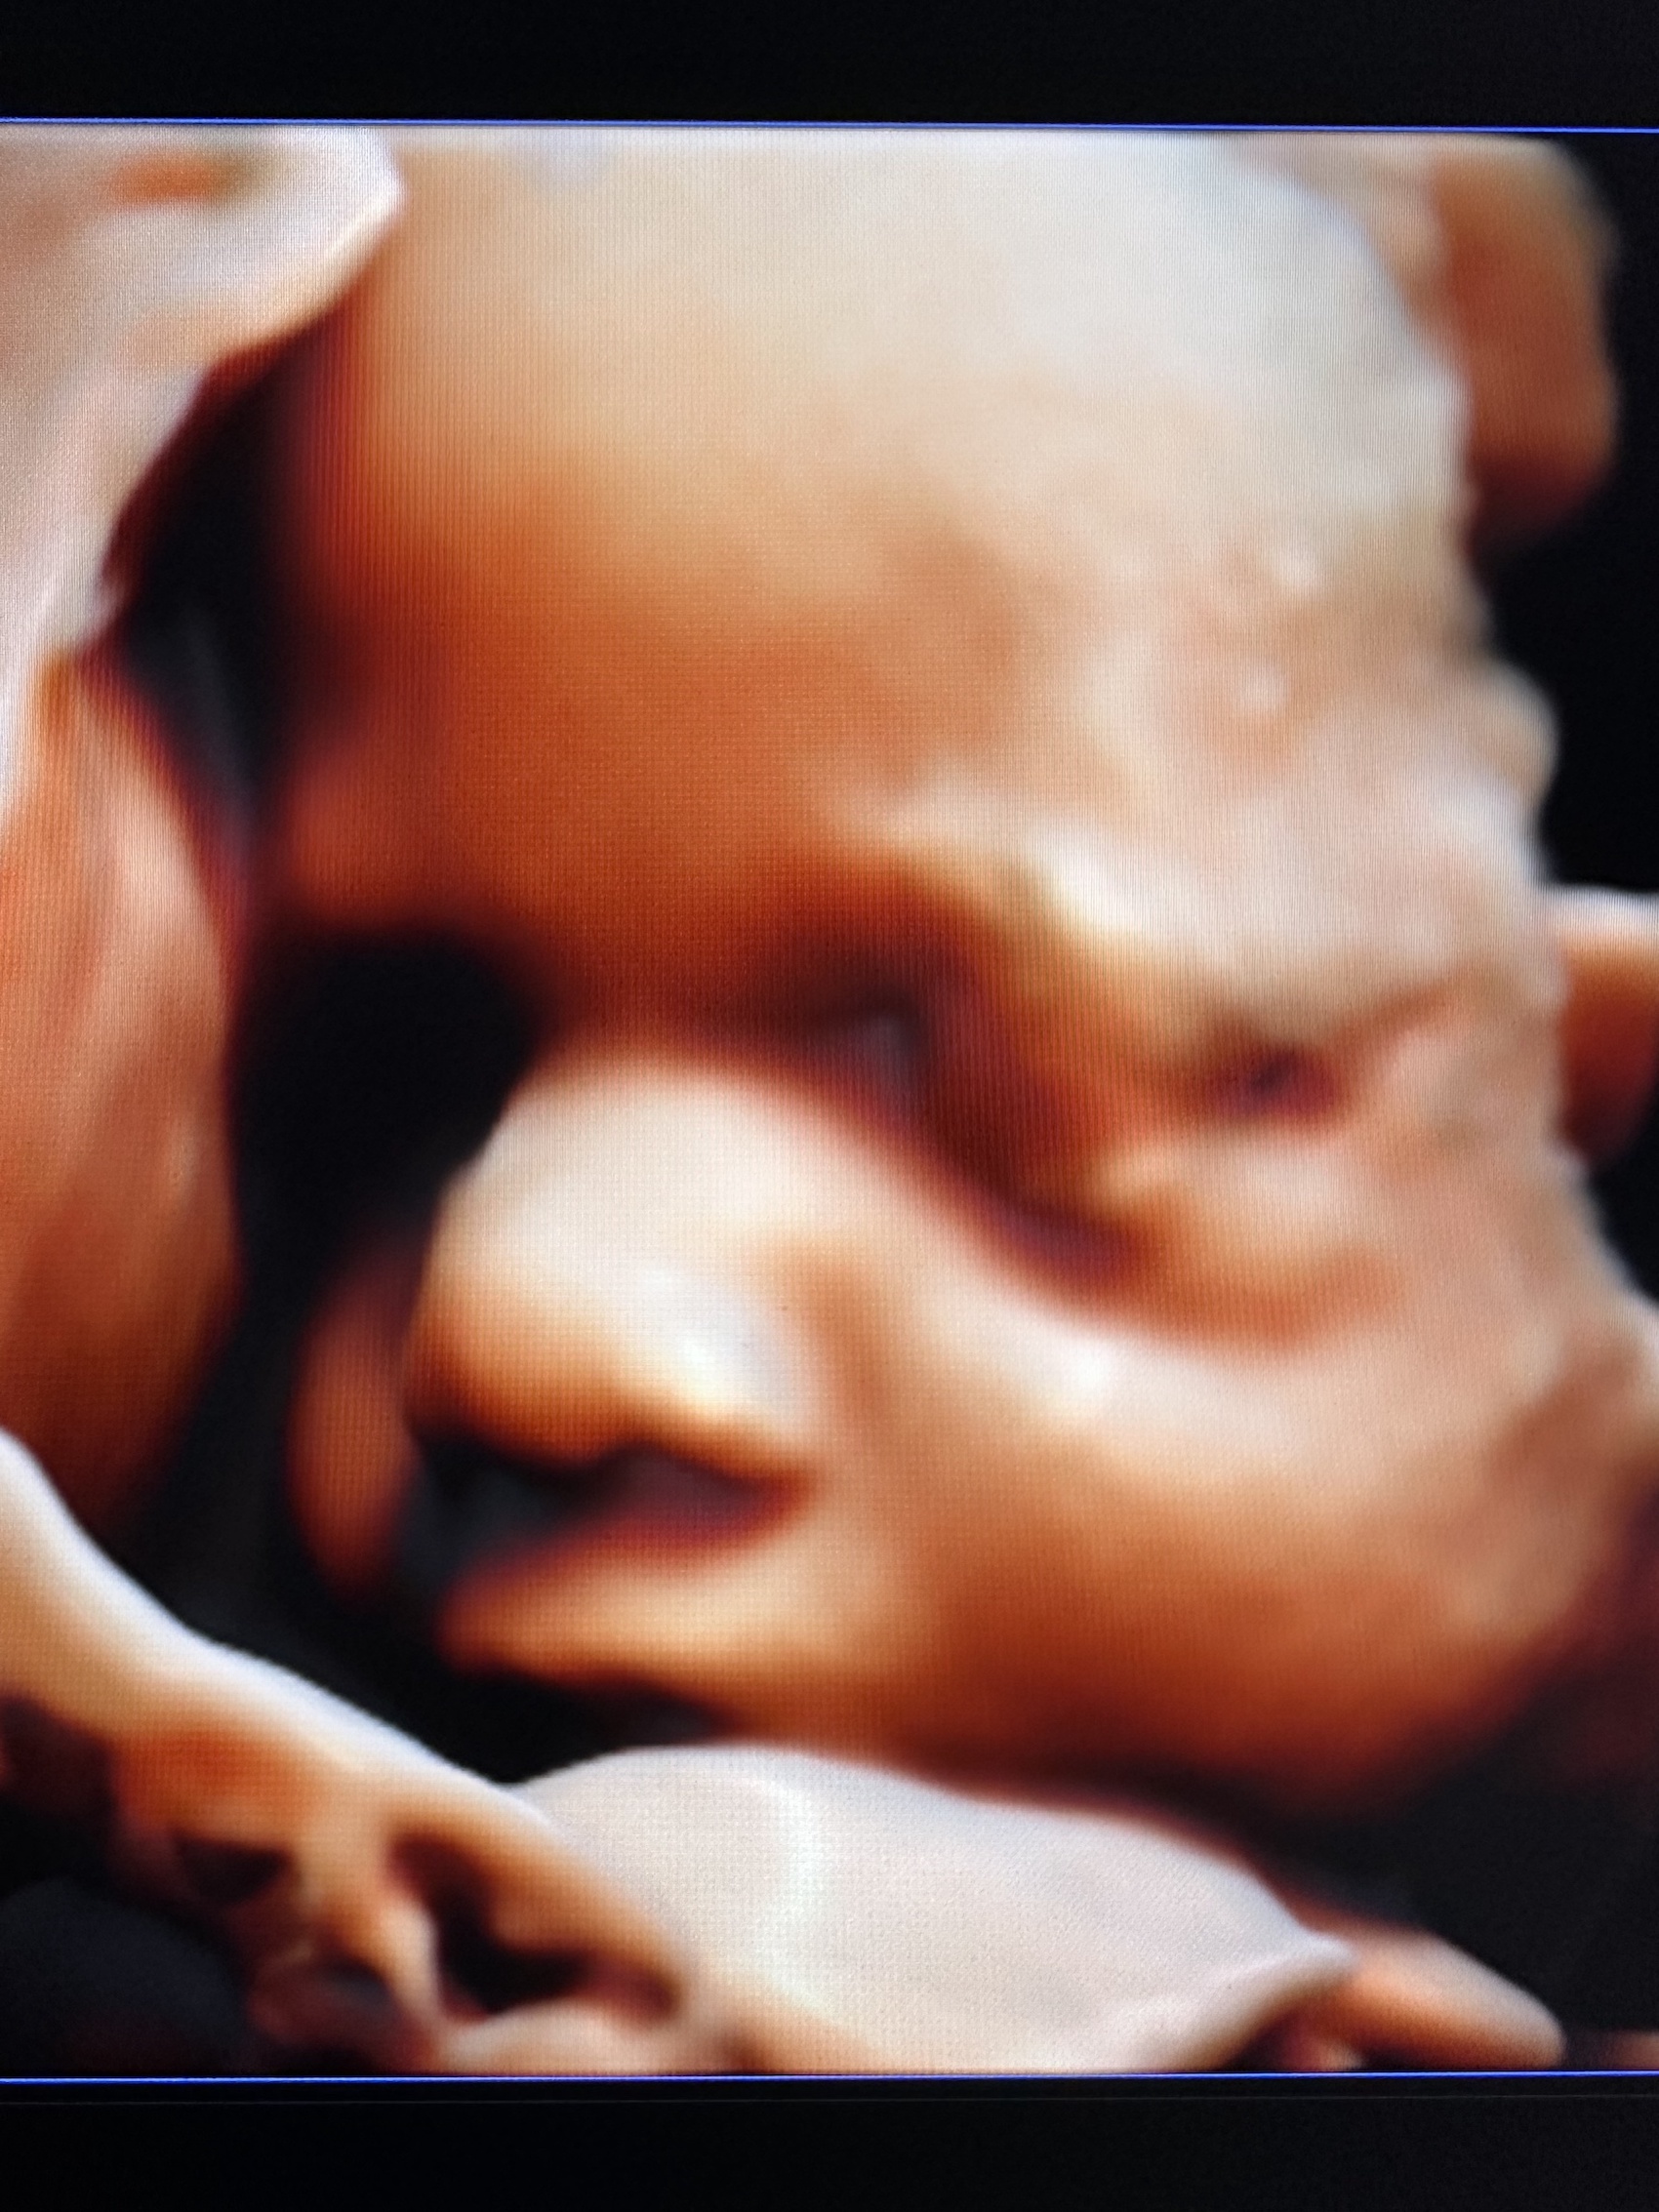

:-) Jestem lekarzem specjalistą w zakresie ginekologii i położnictwa , w ramach prowadzonej praktyki ginekologicznej staram się świadczyć kompleksowe porady lekarskie najwyższym poziomie ,w oparciu o najwyższe standardy jak i przy pomocy najnowszego sprzętu medycznego. W trakcie pracy zawodowej uzyskałem kolejno tytuły specjalisty I stopnia , a później specjalisty II stopnia , a także uzyskałem dodatkowe uprawnienia

CERTYFIKAT BADAŃ PRENATALNYCH POLSKIEGO TOWARZYSTWA GINEKOLOGÓW I POŁOŻNIKÓW

CERTYFIKAT BADAŃ PRENATALNYCH FMF ( FETAL MEDICINE FOUNDATION - LONDYN )

W ramach praktyki wykonuję pełen zakres badań ultrasonograficznych w zakresie ginekologii jak i położnictwa wraz z badaniami prenatalnymi , badaniami ultrasonograficznymi piersi .

Zdjęcia i filmy